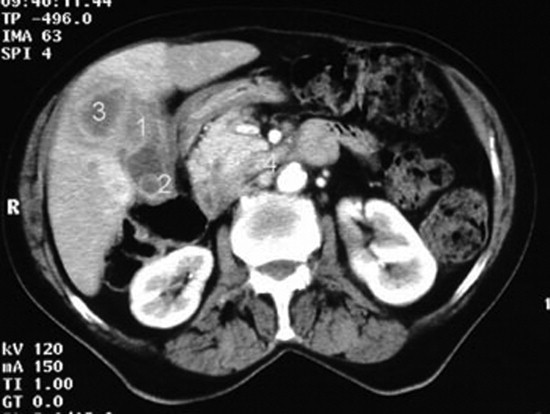

Τα τελευταία χρόνια έχει παρατηρηθεί αύξηση της συχνότητας των τυχαία ανακαλυπτόμενων βλαβών του ήπατος και των χοληφόρων, λόγω της αυξανόμενης χρήσης απεικονιστικών μεθόδων.

Η πλειονότητα των βλαβών ...